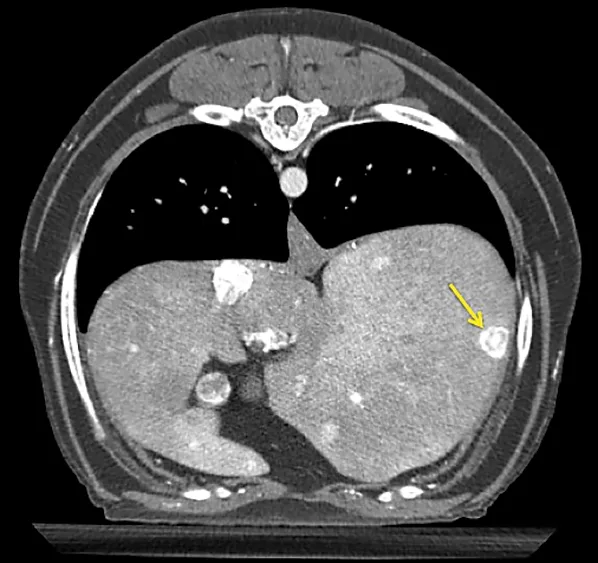

A thoracoabdominal dual-phase CT scan was performed with the goals of further evaluating the pancreatic nodule, ruling out obvious metastatic disease, and planning for possible surgery. The CT scan revealed a 1.8 × 2.6-cm nodule in the body of the pancreas that demonstrated marked neovascularization in the early arterial phase and mild peripheral contrast enhancement relative to the remainder of the pancreas in the main arterial and portal phase scans (Figure 2). A strong contrast-enhancing liver nodule was noted in the arterial phase of the CT angiogram (Figure 3). Other hepatic nodules noted on ultrasound were not visualized in the arterial or mixed portal/venous angiographic phases. No evidence of nodular pulmonary metastasis was evident.

Figure 2 Arterial phase CT angiograph image demonstrating a strongly contrast-enhancing pancreatic nodule (arrow)